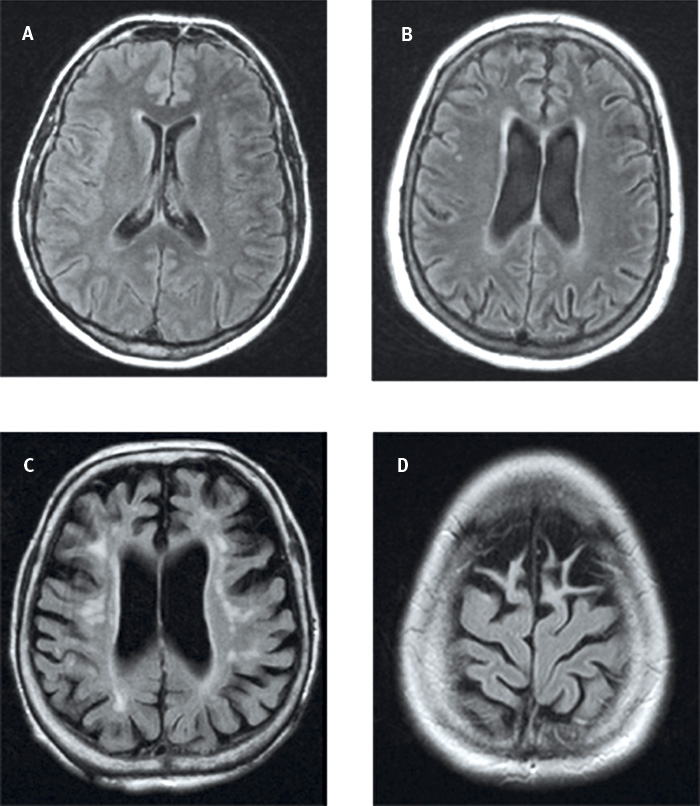

Global kortikal atrofi, GCA. Visuell bedömning av kortikal atrofi speglar inte bara den totala cerebrala atrofigraden utan även den lobära och den regionala atrofigraden. Vidgning av sulci på MR eller DT kan vara sekundär till atrofi av kortex och/eller vit substans, varför beteckningen kortikal atrofi egentligen endast bör användas när man mäter tjockleken på kortex. Vidgning av sulci och volymförlust av gyri bedöms enligt en 4-gradig skala, GCA 0–3 [19]. Normala förhållanden utan vidgning av sulci är GCA 0, lätt vidgning av sulci är GCA 1, volymförlust i gyri är GCA 2 och uttalad vidgning av sulci med uttalad volymförlust är GCA 3 (Figur 3).

Figur 3. Global kortikal atrofi: GCA 0 (A) , GCA 1 (B) , GCA 2 (C)  och GCA 3 (D),  endast bifrontalt.